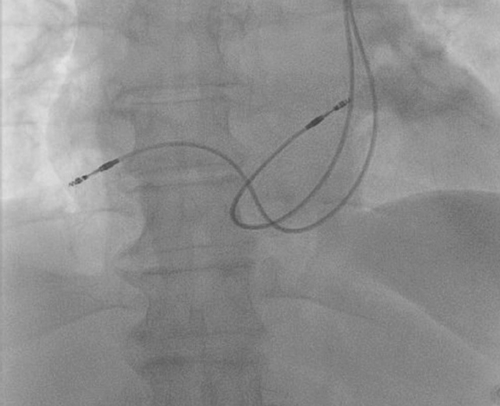

برای غلبه بر چالش‌ها، پزشکان از سیم ۵۸ سانتی‌متری با فیکساسیون غیرفعال استفاده کردند، اما به دلیل دشواری تثبیت، به سیم فعال تغییر دادند. استایلت انتهایی به شکل L تیز اصلاح شد تا سیم از سینوس کرونری عبور کند و به بطن راست برسد. سیم بطنی در خروجی بطن راست (RVOT) و سیم دهلیزی در آپاندیس دهلیز راست قرار گرفت. موقعیت نهایی با فلوروسکوپی تایید شد.

این ناهنجاری اغلب با defect‌های قلبی مادرزادی (۴۶ درصد موارد) و اختلالات هدایتی همراه است. تشخیص پیش از عمل با اکوکاردیوگرافی ضروری است، که علائمی مانند سینوس کرونری گشاد را نشان می‌دهد. روش‌های کاشت در PLSVC نیازمند سیم‌های بلندتر و مسیرهای مدارگونه است.